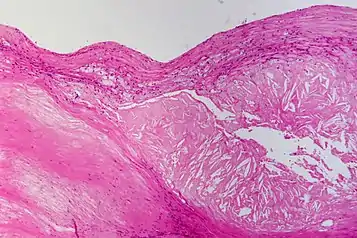

![]() | Osteochondroma | Perichondrium covering the cartilage cap, which merged into the underlying spongiosa. | Category: Histopathology of osteochondroma | osteochondroma |